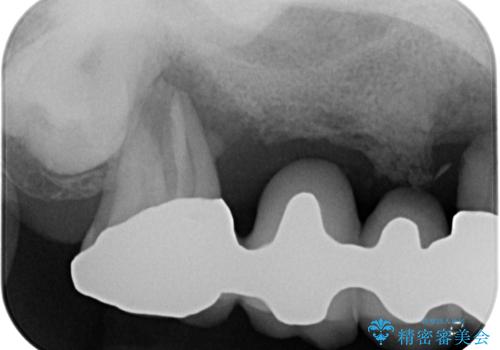

- 奥歯がぐらぐらして噛めないとのことで来院された患者様です。

ブリッジの土台となっている歯は全て抜歯が必要な状態であったため、事前に仮歯を用意して、極力抜歯と同時にインプラントを埋入し、速やかに仮歯を装着して噛めるように処置を進めて行くこととしました。

手前の歯は骨の欠損が著しいため、抜歯後暫く待ってから埋入を行うこととしました。

後方2本を先に埋入し、即日で仮歯を装着しましたが、徐々にインプラントが骨内で緩んでしまい、手前のインプラント埋入時に再埋入することとなりました。